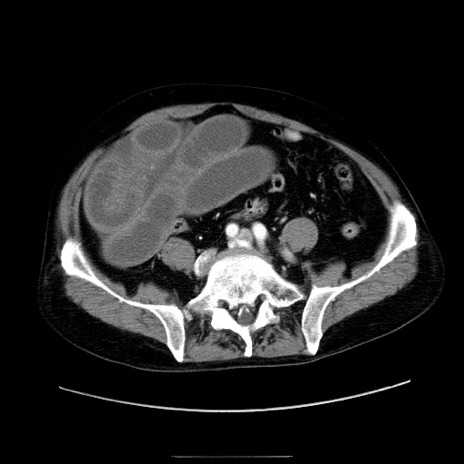

症例30(横断像)

【症例】80歳代男性

【主訴】臍周囲痛

【現病歴】約6時間前から臍下部痛が出現。次第に腹部膨隆・背部痛も生じてきたため来院。背部痛の場所は変化しない。

【既往歴】腎盂腎炎

【身体所見】意識清明、BT 36.3℃、BP  131/87mmHg、P 87bpm、SpO2 100%(RA)、臍周囲自発痛・圧痛あり、反跳痛なし、自発痛部位に一致して板状硬あり、腹部膨隆、腸雑音減弱、CVA tenderness両側陰性。

【データ】WBC 19600、CRP 0.33